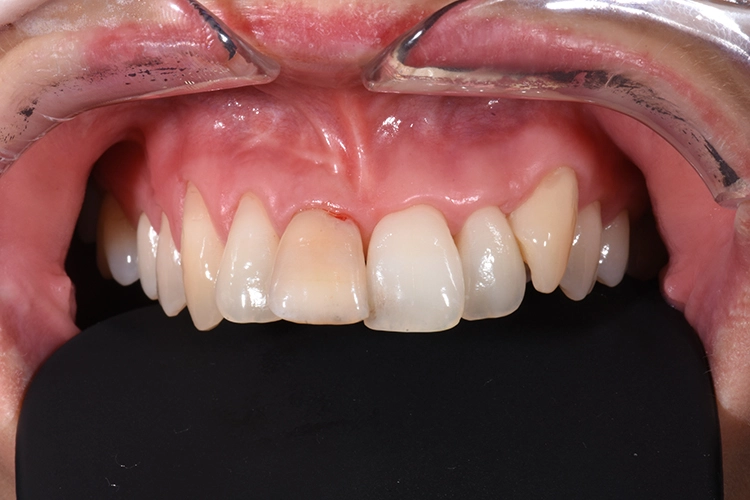

Deutlich auffallend und für die Patientin sehr wichtig war die anatomisch individuelle Zahnstellung des Zahnes 11. Um dem Wunsch der Patientin auf eine für ihr Umfeld unauffällige Behandlung gerecht zu werden, entschieden wir uns gemeinsam für eine Sofortimplantation mit einer provisorischen Sofortversorgung des Implantates. Kein Provisorium kommt der Natur so nah wie die Natur selbst und daher planten wir die Umarbeitung der Zahnkrone 11.

Nach der Lokalanästhesie wurde zunächst ein Kunststoff Jig hergestellt, der die Inzisalkante des Zahnes 11 mit denen der Nachbarzähne verbindet. Dieser dient zur späteren Positionierung der Zahnkrone, wenn diese zum Provisorium umgearbeitet wird und mit dem Implantat verbunden wird. Dieser Schritt ist besonders wichtig, da es für ein unauffälliges postoperatives Ergebnis auf die korrekte Positionierung des Zahnes ankommt und die Positionierungshelfer das Handling und den adhäsiven Verbund unglaublich vereinfacht (Abb. 20 und 21).

Die erste Verbindung dient ausschließlich der dreidimensionalen Fixierung in Relation zum Abutment. Die weitere Ausarbeitung der Krone erfolgt extraoral, wobei auf die Gestaltung eines physiologischen Emergenzprofils geachtet werden muss. Anschließend wird das Provisorium einfach auf die Implantat-Basis geklickt, das Bild zeigt die Situation unmittelbar nach der Implantation (Abb. 23-28).